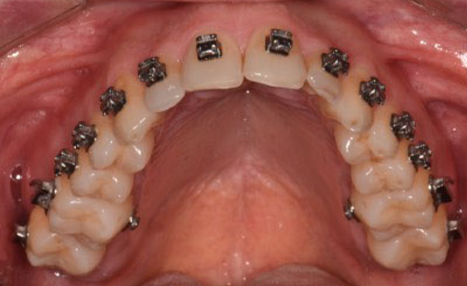

The final 4 months were focused on arch coordination and detailling.

Individually coordinated stainless steel archwires, using the WALA ridge described by Dr. Andrews as the reference

(image: Finishing wires)